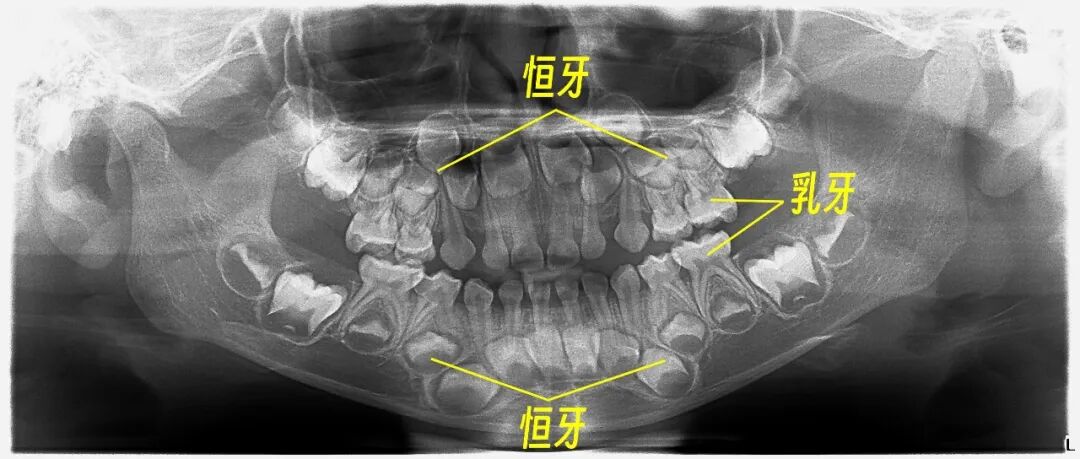

你以为婴儿是在出生后6个月左右才长牙?错了。实际上,怀孕2个月左右,婴儿的牙齿发育钙化就开始了。

在出生前,20颗乳牙已基本形成,只是还未萌出;直到出生6个月之后,才依次萌出。恒牙也不是6岁后才开始生长的,而是从胚胎第4-5个月时,牙胚就开始发育了。